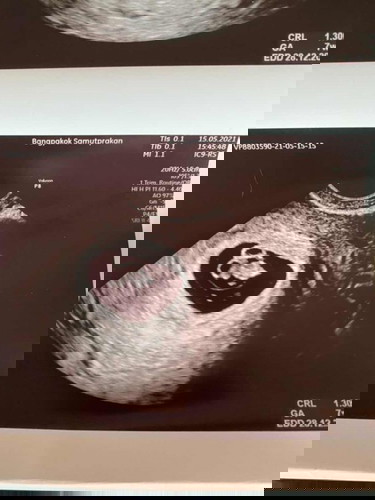

หลังจากที่กังวลมานาน ตั้งแต่รู้ว่าท้อง กลัวว่าจะท้องลม หรือ ท้องนอกมดลูก เนื่องจากไม่มีอาการแพ้ใดๆ ในที่สุด วันนี้ #7w4d ก็เห็นแล้วจ้า โล่งอกเป็นปลิดทิ้ง หัวใจน้องเต้นเร็วมาก พัฒนาตามเกณฑ์ คุณแม่ปลื้มปริ่มค่ะ ดวงใจน้อยของเรา 😍 #ซาวน์แบบสอด #ท้องแรกคะ